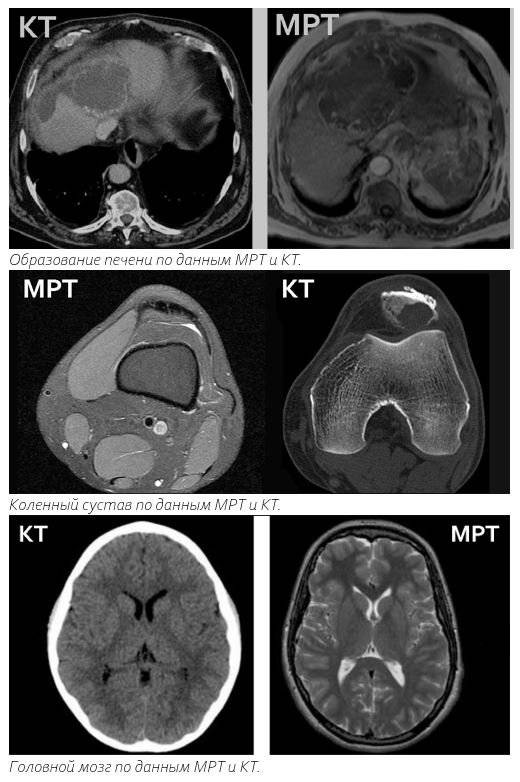

Орган | МРТ | КТ |

Головной мозг | Лучше, так как оценивается больше видов патологии | Назначается при подозрении на перелом черепа или в экстренной ситуации |

Позвоночник | Лучше, так как оцениваются мелкие детали; способна обнаружить отек и опухоли | Назначается при подозрении на мелкий перелом или в экстренной ситуации |

Придаточные пазухи носа | Может применяться у детей, беременных женщин, пациентов, не желающих облучаться | Лучше, так как быстрее и есть возможность оценить костные структуры |

Легкие | Может подойти для оценки образований средостения, динамического наблюдения за опухолью | «Золотой стандарт» диагностики заболеваний легких |

Брюшная полость | Более детализированная картина образований, ограничения в исследовании кишки | Плюсы: скорость исследования и обхват исследуемой области |

Малый таз | Является «золотым стандартом» в оценки изменений всех органов малого таза | Может назначаться в экстренных случаях |

Каждый из рассмотренных диагностических методов имеет свои особенности и область применения. МРТ даст более четкое изображение мягких тканей, в то время как КТ покажет кальций в костных структурах, чего не способна сделать магнитно-резонансная томография.